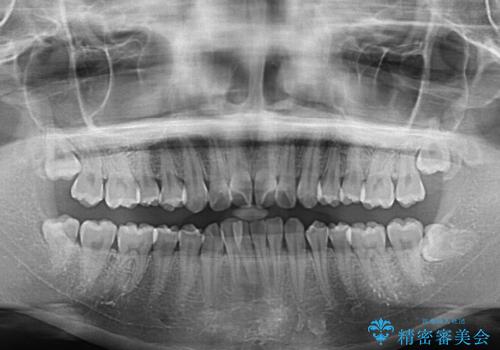

- 前歯のデコボコを気にして来院された患者様です。

前歯が重なっていることで口元が閉じにくくなっていたため、歯列全体の側方への拡大と、歯と歯の間を少し削ってスペースを獲得することとしました。

下顎前歯は後戻りを起こしやすいため、舌側を細いワイヤーで固定し、マウスピース型リテーナーで保定を行うこととしました。